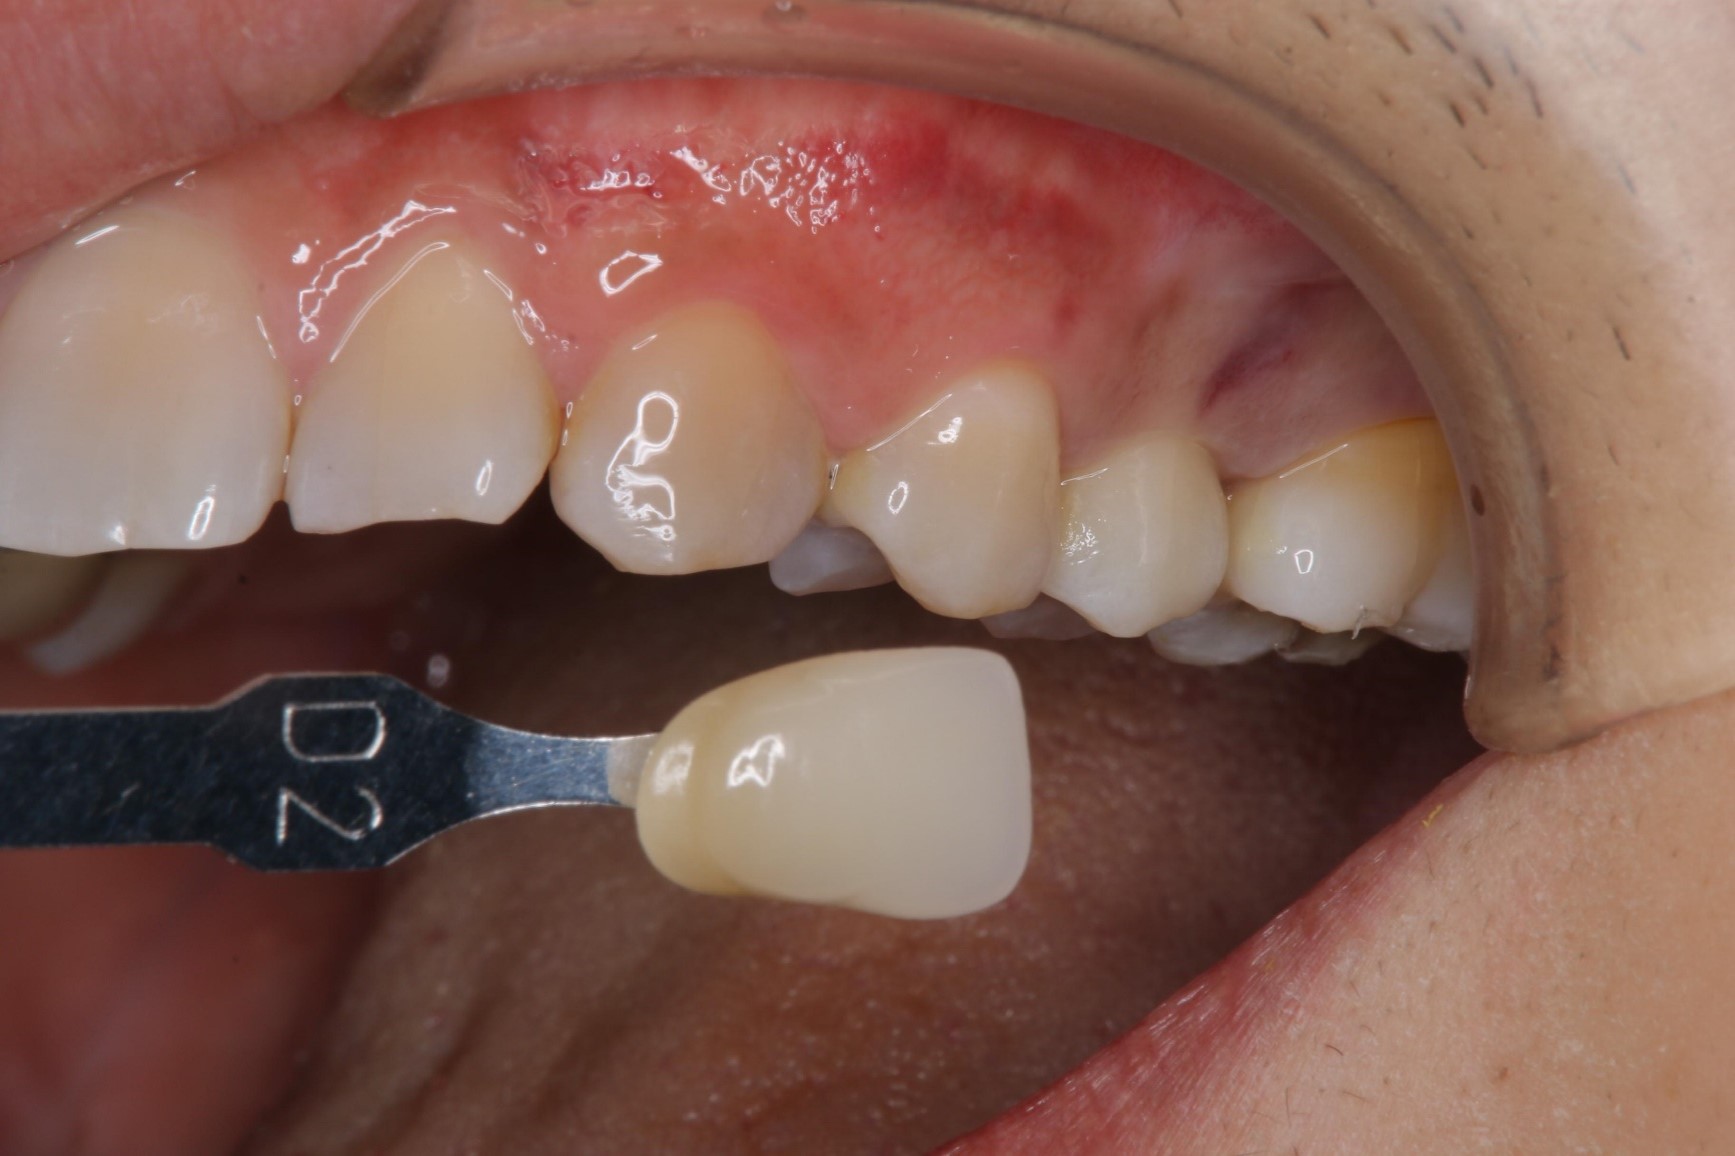

比色照相